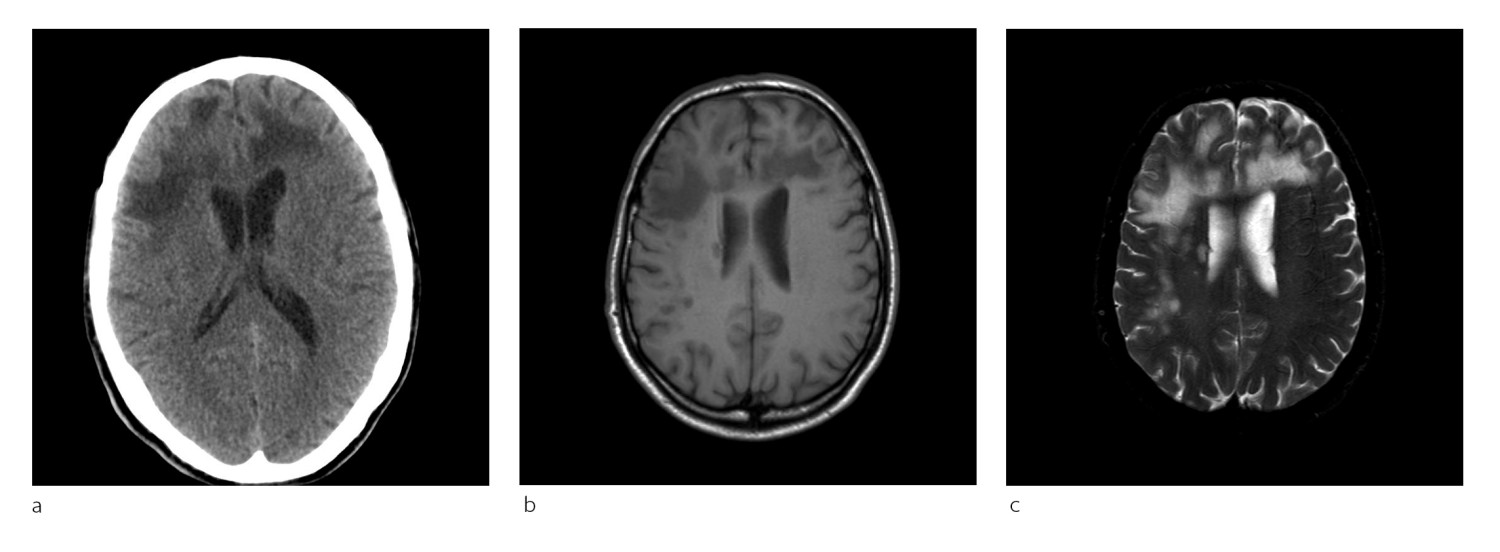

Pasient 2. En kvinne i 50-årene med attakkpreget multippel sklerose var blitt behandlet med natalizumab (Tysabri) over flere år da hun fikk påvist diskrete forandringer på en MR-undersøkelse. Hun hadde da ikke hatt tegn til sykdomsaktivitet på flere år. JCV-antistoff var blitt påvist i serum to år tidligere, men indeks var ikke tilgjengelig på dette tidspunktet. Natalizumab ble seponert, men pasienten utviklet etter hvert likevel ustøhet og dobbeltsyn, og MR-undersøkelse to måneder senere viste betydelig økning av forandringer (fig 2a). Det var en inhomogen høyattenuerende forandring i høyre lillehjernestilk som ikke er lett å skille fra en forandringer ved multippel sklerose. PCR-undersøkelse av JCV-DNA avdekket 1 173 kopier/ml i spinalvæske.

Plasmaferesebehandling ble gitt, men symptomene progredierte. Ny MR-undersøkelse tre uker senere viste kontrastladende lesjoner, forenlig med immunrekonstitusjonsinflammasjonssyndrom (fig 2b). Pasienten fikk høydose metylprednisolon (Solu-medrol), med påfølgende remisjon. Hun ble frisk fra progredierende multifokal leukoencefalopati, men fikk sekvele.